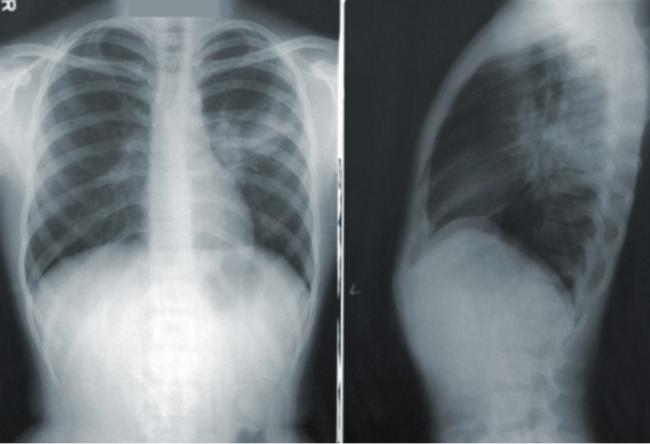

癌症幸存者MaryAnn Bradley分享说,2014年,她在左侧颈部感到疼痛,医生们最终在她的右上肺发现了一个2.5厘米的肿瘤。